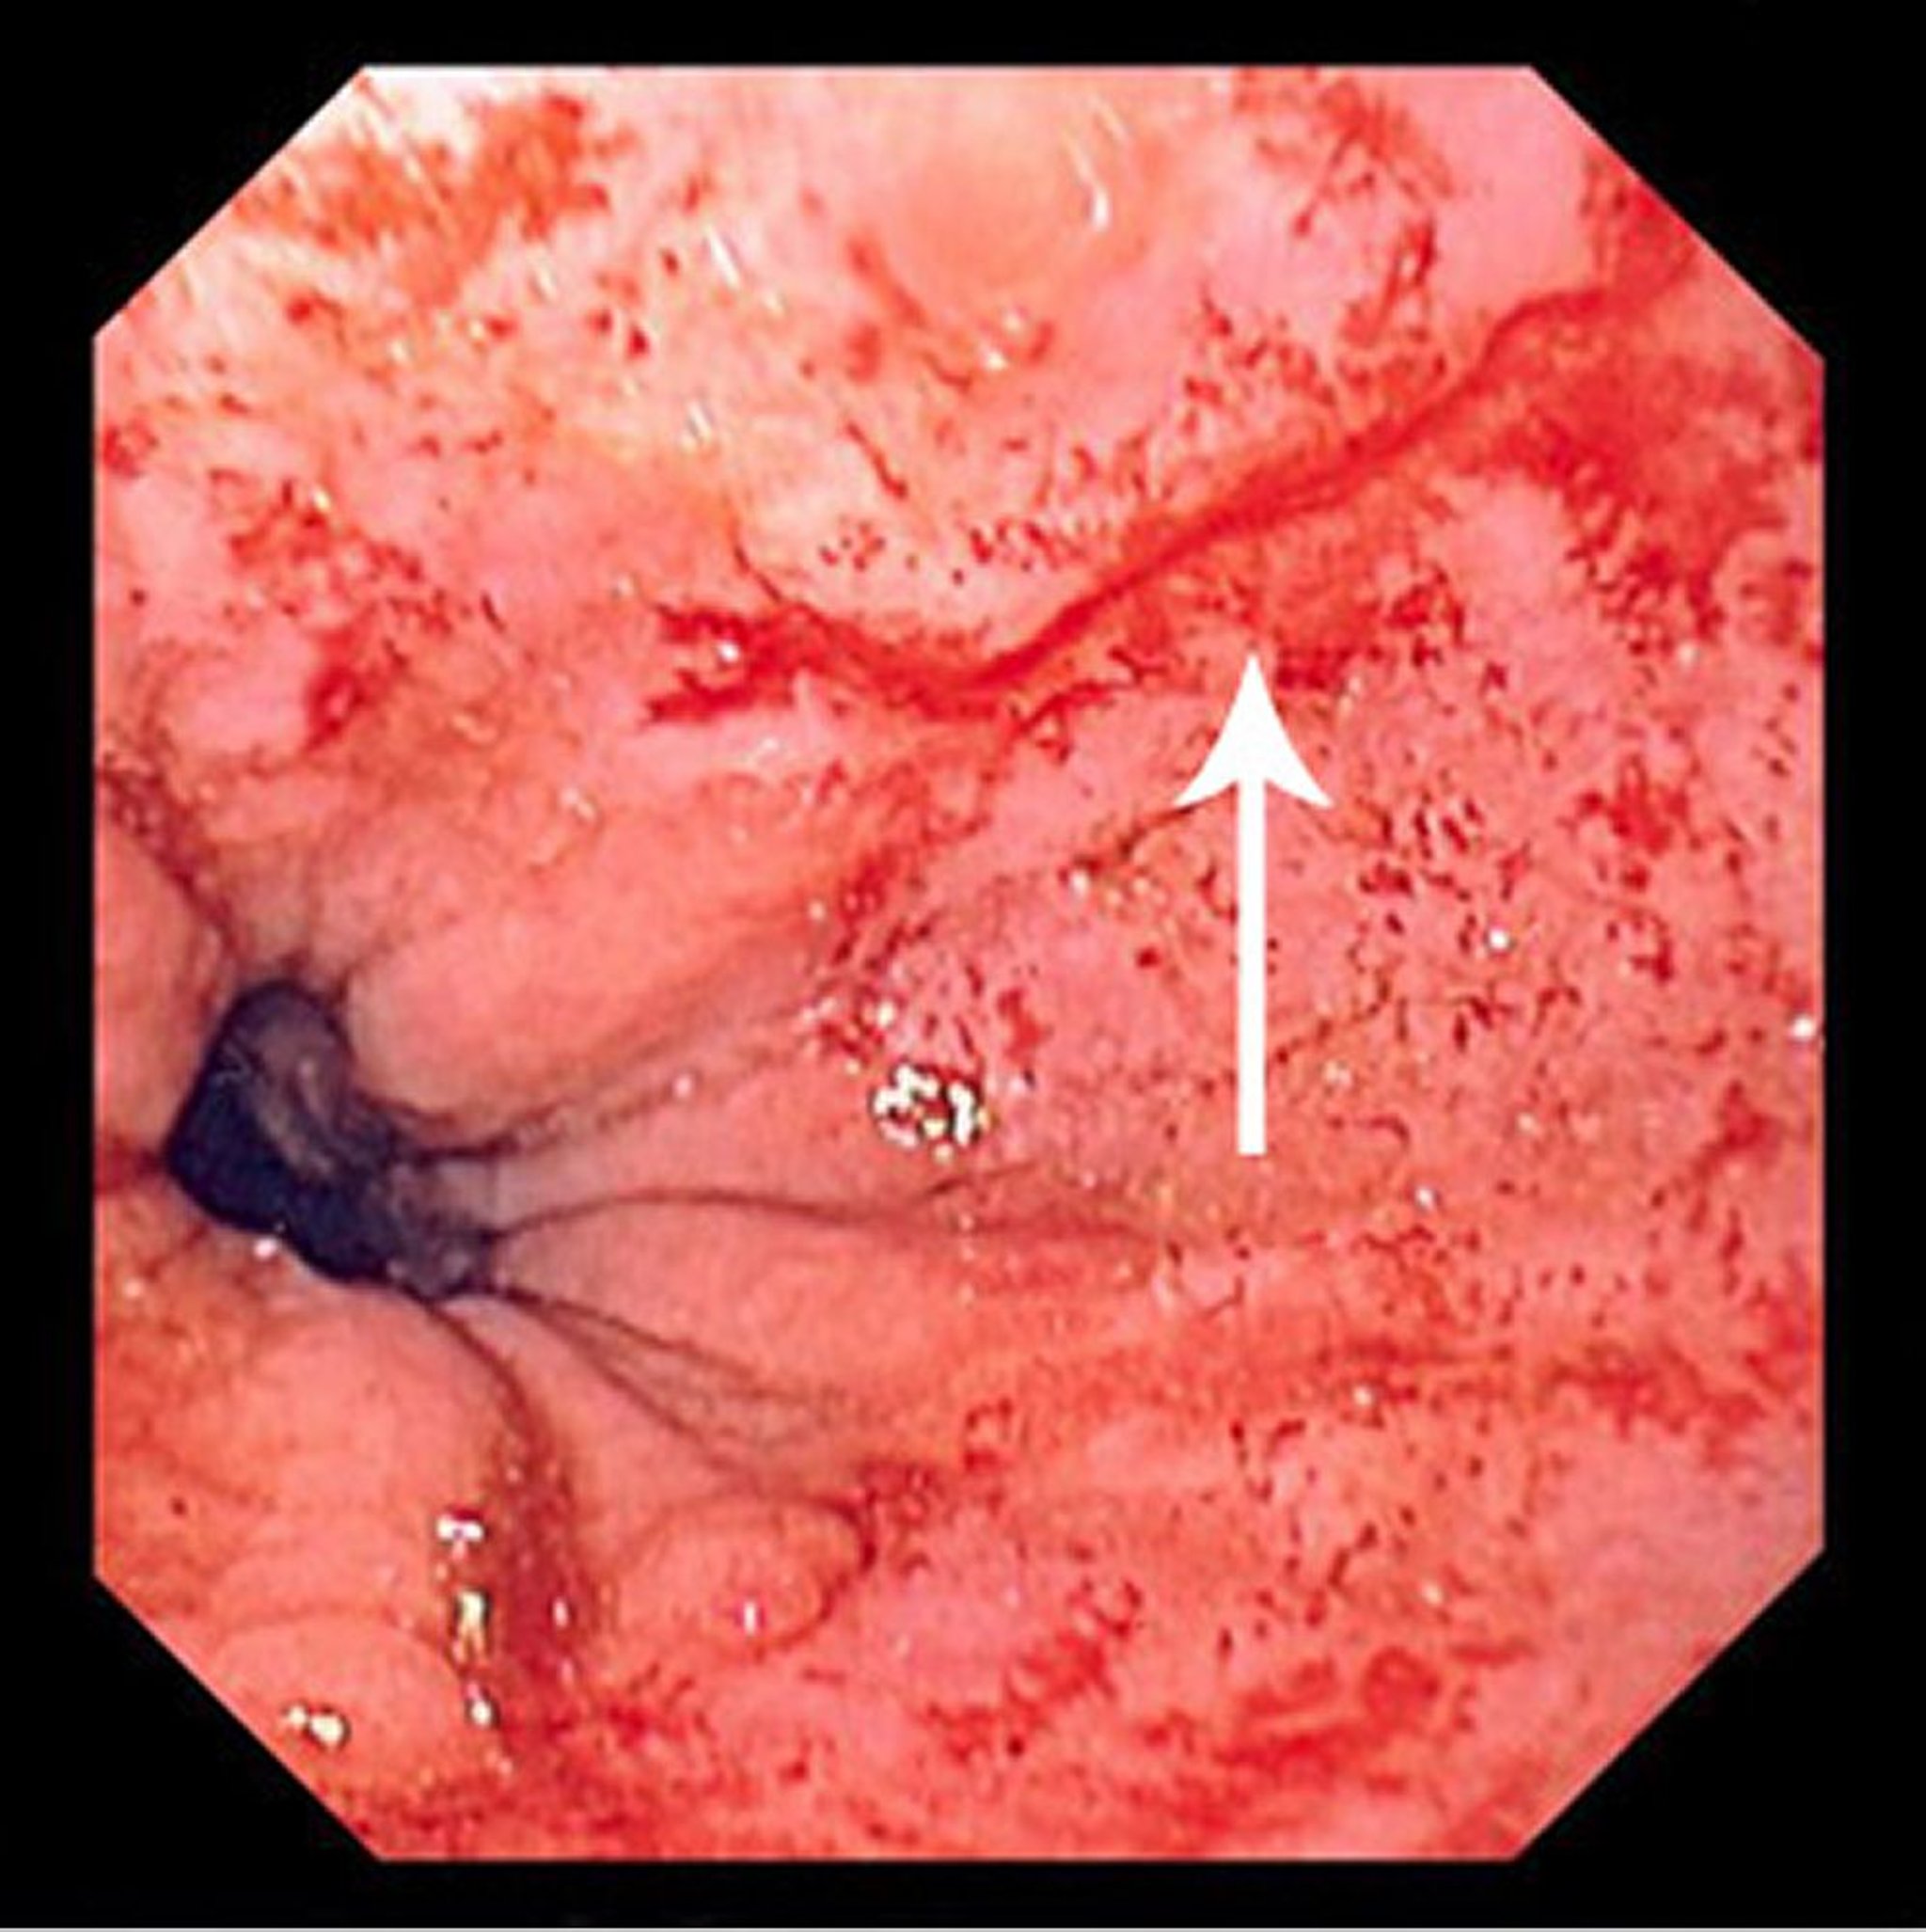

Синдром Мэллори-Вейса

На этом изображении показан тонкий линейный разрыв (отмеченный стрелкой), начинающийся чуть выше зоны перехода плоского эпителия пищевода в цилиндрический эпителий и простирающийся проксимально.

Image provided by David M. Martin, MD.